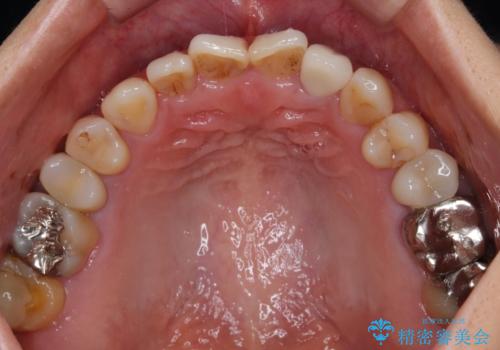

根管治療後速やかに痛みが消退し、6ヶ月後のレントゲン写真では、根尖部の病変がほぼなくなっていることが分かりました。